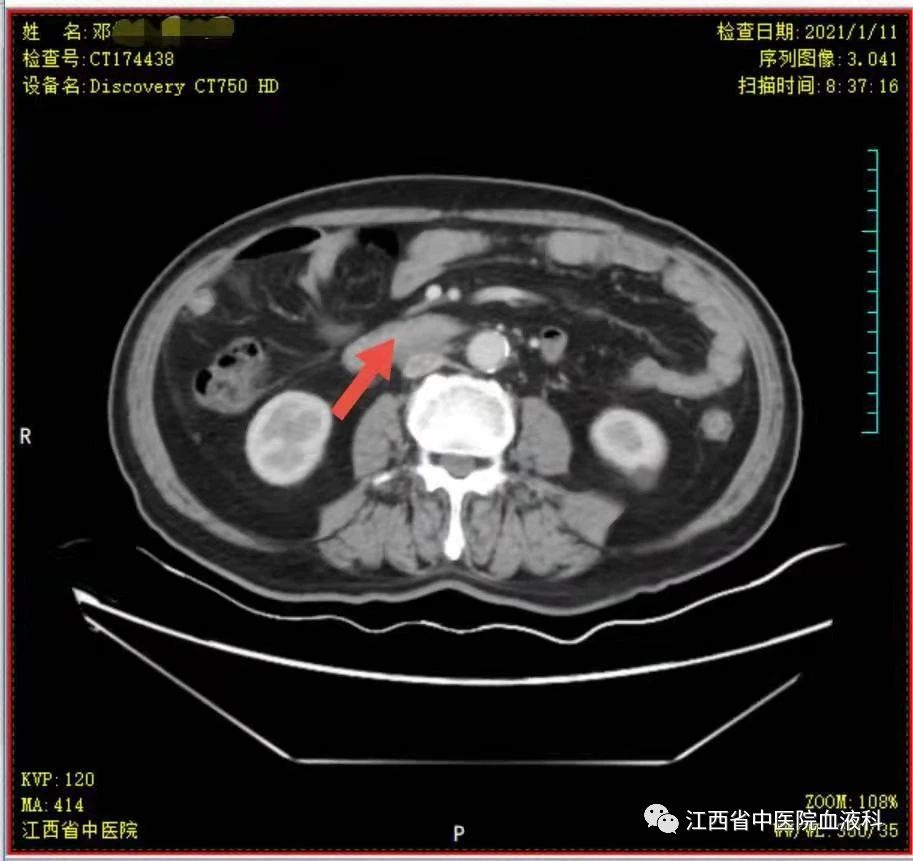

2020年10月中旬邓大爷在家人的陪同下来我科就诊,全腹部增强CT提示:右侧睾丸切除术后复查:1.腹膜后(胰头后下方)、双侧肾上腺区团块状异常强化影。2.肝左内叶上段小囊肿,双肾小囊肿,较前相仿。3.右侧腹股沟前方、皮下条索、小片影,境界不清,较前减小,拟为术后改变。4.右下腹腔少许钙化淋巴结,较前相仿。因病情危急,考虑邓大爷高龄、体能差、窦性心动过缓(平均心率50次/分)心脏功能差等情况,经讨论于2020-10-24起第一次行减剂量方案R-miniCHOP(利妥昔单抗700mg d0、环磷酰胺700mg d1、多柔比星40mg d1、长春瑞滨20mg d1、地塞米松10mg d1-5)方案。第一次化疗后评估病情,腹腔瘤体缩小了2/3,取得了很好的治疗效果,可邓大爷心脏却亮起了红灯,经过了积极护心等支持治疗后,大爷心脏功能有所恢复。遂于2020-11-19、2020-12-10行2次R-miniCOP方案(去除了具有心脏毒性的多柔比星),三次化疗结束后予评估病情,提示腹腔包块明显缩小,淋巴瘤病情有所好转。